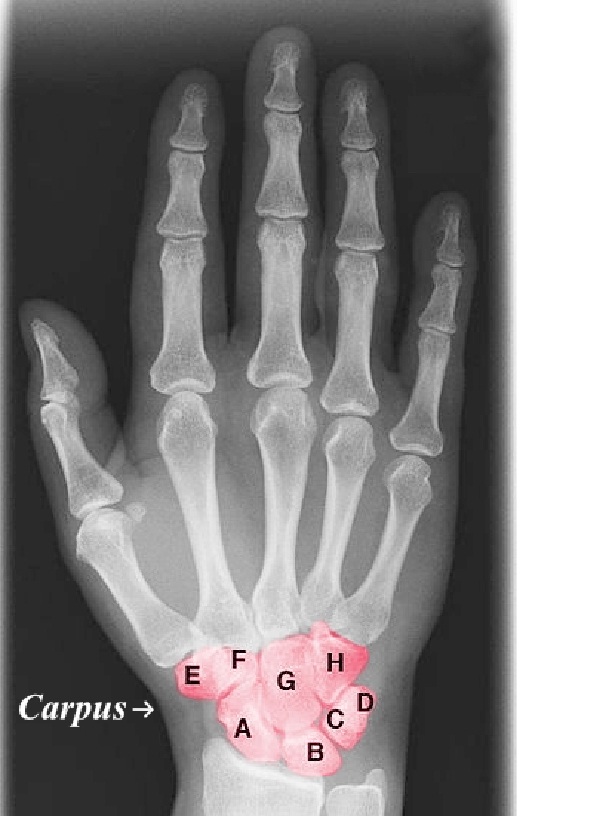

Palm Tangan Manusia - Gambar vektor gratis di Pixabay Gambar Tangan Manusia Beserta Fungsi Setiap Bagiannya • Hello Sehat Misteri Tubuh Manusia, Kenapa Kita Memiliki 10 Jari Tangan dan Kaki? Halaman all - Kompas.com Jari Tangan Manusia Bayangan - Gambar vektor gratis di Pixabay Filosofi Lima Jari Tangan - Kompasiana.com Gambar : manusia, Buka, Anak laki-laki, telapak tangan, sikap, rak, lengan, menangani, kosong, bookmark, membantu, alat tangan, di, senjata, meregang, memesan, naik, 5, sisi, lima, pengangkatan, memimpin, Salam pembuka, tersedia, sukarelawan, panduan, Jari Tangan Manusia - Gambar vektor gratis di Pixabay 6 Perkara yang Bisa Dibaca Lewat Jari Tangan Manusia | FEED - MERDEKA.COM Ikon Jari Tangan, Jari, orang, lilin, lengan png | PNGWing Mengapa Manusia Memiliki 10 Jari Tangan dan 10 Jari Kaki? - kumparan.com JARI TANGAN - Gideon Yusdianto Ini Fungsi Setiap Bagian Tangan Manusia yang Perlu Diketahui Makna di Balik 6 Simbol Jari di Sejumlah Negara - Global Liputan6.com Mengapa Manusia Punya 10 Jari Tangan? Ini Faktanya - Tribun Bali Rahasia 5 jari tangan manusia (Muslim masuk) | KASKUS Jari, Tangan, Tubuh Manusia gambar png Gambar Tangan Manusia Beserta Fungsi Setiap Bagiannya • Hello Sehat Rahasia di Balik Kekuatan Tangan Manusia - Citizen6 Liputan6.com Tutorial Cara Menggambar Tangan Anime untuk Pemula Jangan Salah, Fungsi Tulang Jari Tangan Ini Perlu Diketahui SETAN ANGKAT DULANG: rahsia lima jari? Jalur Saraf Terpenting di daerah Jari dan Telapak Tangan Manusia Gambar Tangan Manusia Beserta Fungsi Setiap Bagiannya • Hello Sehat Puncta 30.03.20: Menuding Orang Lain | SESAWI.NET Gambar Tangan Manusia Beserta Fungsi Setiap Bagiannya • Hello Sehat Lima Jari Membuka Telapak Tangan Asli Yang Dilukis, Tangan Terbuka Lima Jari Telapak Tangan Realistis, Telapak Tangan Manusia, Telapak Tangan Primata PNG Transparan Gambar Clipart dan File PSD untuk Unduh Gratis Gambar Tangan Manusia Beserta Fungsi Setiap Bagiannya • Hello Sehat Gambar-gambar Tangan dan Fungsi Manusia Setiap Bahagian / Maklumat Kesihatan | Petua perubatan dan maklumat kesihatan yang berguna. Jari - Wikipedia bahasa Indonesia, ensiklopedia bebas Mengukur Tingkat Kecerdasam Lewat jari Tangan | TAMAN PENDIDIKAN PRASEKOLAH CAHAYA INSAN CENDEKIA Gambar Tangan Manusia Beserta Fungsi Setiap Bagiannya • Hello Sehat Salam Gambar Tangan 3 Jari, HD Png Download , Transparent Png Image - PNGitem Gambar Gaya Kartun Menunjuk Isyarat Tangan, Menunjuk, Tangan Manusia, Vektor Isyarat PNG dan Vektor untuk Muat turun Percuma Ikon Jari Tangan, Jari, orang, lilin, lengan png | PNGWing Daftar Tulang Di Area Jari Tangan Dan Telapak Tangan Jari Kaki Wanita Ini Nampak Seperti Jari Tangan Manusia Di Taiwan 4 Gambar | Waktu Solat Dot Net Corat-Coret izani fatwa: Falsafah / Filosofi 5 Jari Manusia Dalam Kehidupan Gambar-gambar Tangan dan Fungsi Manusia Setiap Bahagian / Maklumat Kesihatan | Petua perubatan dan maklumat kesihatan yang berguna. Panjang Jari Tangan Tentukan Kecerdasan? – Belajar Kreatif Jari Kaki Wanita Ini Nampak Seperti Jari Tangan Manusia Di Taiwan 4 Gambar | Waktu Solat Dot Net Gambar Isyarat Jari Tangan Kiri, Gerak Isyarat, Jari, Telapak Tangan PNG dan PSD untuk Muat turun Percuma foto, orang, telapak tangan kanan, tangan, jari, ibu jari, jari telunjuk, jari tengah, CC0, domain publik, bebas royalti | Piqsels Palm Tangan Jari Ibu - Gambar vektor gratis di Pixabay Gambar : tangan, orang-orang, wanita, kaki, jari, sepasang, berwarna merah muda, lengan, kuku, bibir, manikur, tubuh manusia, hidung, gambar, kepala, organ, smilies, angka tongkat 2248x2248 - - 1195924 - Galeri Foto - PxHere Fungsi Tulang Jari Tangan Pada Manusia Adalah Gambar Letaknya jari manis – Pringsewu Resto Gambar Manusia Menekan Tangan Di Merah Bermain Butang, Indeks, Jari, Tangan PNG dan Vektor untuk Muat turun Percuma Tangan, Jari, Warna Kulit Manusia gambar png Jari Kaki Wanita Ini Nampak Seperti Jari Tangan Manusia Di Taiwan (4 Gambar) - Api Viral Ada Hubungannya, Mr P dengan Jari Tangan, Kaki dan Ereksi - Tribunnews.com Mobile Gambar Gerakan Jari Belakang Tangan Tangan Manusia Ilustrasi, Pergerakan Jari, Belakang Tangan, Tangan Manusia PNG dan PSD untuk Muat turun Percuma Gambar : manusia, orang-orang, wanita, jari, sepasang, pasangan, bersama, lengan, berpegangan tangan, cincin, emosi, interaksi, merasakan 5616x3744 - - 925748 - Galeri Foto - PxHere Jari Kaki Jempol kaki manusia, kuku, tangan, kaki png | PNGEgg Jari Kaki Wanita Ini Nampak Seperti Jari Tangan Manusia Di Taiwan (4 Gambar) - Api Viral Tutorial Cara Menggambar Tangan Anime untuk Pemula Tangan Dengan Jari, Digambar Tangan, Manusia, Gambar PNG Transparan Gambar Clipart dan File PSD untuk Unduh Gratis Inilah Jenis dan Fungsi Tulang Telapak Tangan Manusia Gambar-gambar Tangan dan Fungsi Manusia Setiap Bahagian / Maklumat Kesihatan | Petua perubatan dan maklumat kesihatan yang berguna. 7 Jenis Garis Tangan Calon Orang Kaya - Tokopedia Blog Gambar : tangan, manusia, awan, langit, sinar matahari, bagian, musim panas, pria, tanda, jari, simbol, sikap, biru, bisnis, lengan, merapatkan, cerah, awan-awan, kebahagiaan, konseptual, iya nih, ekspresi, konsep, naik, indah, baik, tubuh, Jempol, Tangan, Pria gambar png Jari Tangan Manusia - Gambar vektor gratis di Pixabay Ibu jari - Wikipedia bahasa Indonesia, ensiklopedia bebas Gambar : tangan, manusia, orang, jari, lengan, nenek, wanita tua, karakter, senior, purnawirawan, usia tua, merasakan, 104 tahun, bintik-bintik usia 5472x3648 - - 619635 - Galeri Foto - PxHere Tutorial Cara Menggambar Tangan Anime untuk Pemula Tangan Jari Lengan Ibu - Gambar vektor gratis di Pixabay 6 Gerakan untuk Menjaga Kekuatan Jari Tangan - Cantik Tempo.co Daftar Tulang Di Area Jari Tangan Dan Telapak Tangan Jari Kaki Wanita Ini Nampak Seperti Jari Tangan Manusia Di Taiwan (4 Gambar) - Api Viral Gambar Tangan Manusia Dengan Jari Yang Menunjuk Atau Menunjuk Ke Arah Anda, Tua, Tangan, Vintaj PNG dan Vektor untuk Muat turun Percuma 10 Gambar Contoh Mutasi Gen Pada Manusia Tangan Manusia Dengan Diperban Jari Pada Latar Belakang Dinding Pirus — Stok Foto © rinzz.hotmail.com #361586296 Tes Kepribadian: Coba Lihat Bentuk Tangan Anda, Karakter Asli Terungkap Waspada Tangan Bergetar Tanpa Henti, Ini 5 Kemungkinan Penyebabnya Terkeren 12 Gambar Tato Cincin- Tato Cincin Pernikahan Romantis For Android Apk Download Gambar Tangan Manusia Orang Cincin Tato Memakai … di 2020 | Cincin, Tato, Gambar Kenali Falsafah Jari-Jari Tangan Manusia - MudhiatulFata Fungsi Tulang Pergelangan Tangan (LENGKAP dengan Gambar dan Penjelasannya) … Tangan Manusia Adalah Menjangkau Untuk Menekan Sesuatu Dengan Jari Telunjuk — Stok Foto © Masteronline2021 #389536920 Tak Perlu Resep Dokter, Memijat Jari Tangan Bisa Stabilkan Kebugaran Tubuh - Tribun Kaltim 10 Isyarat Tangan Ini Punya Banyak Makna, Jangan Sembarangan Mempraktikannya pada Orang Asing tangan, drama, jari, telapak tangan, mencapai, tangan manusia, bagian tubuh manusia, tembakan studio, CC0, domain publik, bebas royalti | Piqsels 3+ Fungsi Tulang Jari Tangan Manusia (Gambar Lengkap) - Ilmusiana Ditahan minta isteri masak tangan manusia | Harian Metro Panjang Jari Tangan Bisa Memprediksi Apakah Anda Jago Olahraga Gambar : orang, sikap, lengan, berpegangan tangan, merapatkan, tubuh manusia, organ, ibu jari, pistol, interaksi, merasakan, tindakan manusia, isyarat tangan 2256x1504 - - 984432 - Galeri Foto - PxHere Tulang Lengan Dan Fungsinya - Pengertian Dan Susunan Gambar Palma Yang Pelik Tapak Tangan Manusia Tapak Kaki Primata Tapak Tangan Biologi, Yang, Nyata, Tapak Tangan Yang Sebenar PNG dan PSD untuk Muat turun Percuma Jari Tangan Manusia Orang - Gambar vektor gratis di Pixabay Tangan Tangan Tubuh Manusia Kerangka manusia, telapak tangan, fotografi, anatomi, Model tangan png | PNGWing Gambar gratis: tangan manusia, orang, tanah, jari, kulit, bayangan 10 Gambar Contoh Mutasi Gen Pada Manusia Fungsi Tulang Telapak Tangan Gambar : tangan, kaki, jari, persahabatan, mulut, tubuh manusia, ulasan, Persatuan, merasakan 3264x2448 - - 551689 - Galeri Foto - PxHere Gambar Tangan Manusia Beserta Fungsi Setiap Bagiannya • Hello Sehat Gambar gratis: jari, tangan, manusia, monokrom Gambar Pendarahan Ikon Ibu Jari Manusia, Terpencil, Tangan, Jari PNG dan Vektor untuk Muat turun Percuma Jari-Jari Manusia Tidak Sama Panjang, Inilah 3 Kemungkinan Penyebabnya - Semua Halaman - Bobo Jari manusia Archives - Kelas Pintar MUDAH!!! CARA MENGGAMBAR TANGAN UNTUK PEMULA - YouTube 4 Fungsi Tulang Pergelangan Tangan pada Tubuh Manusia